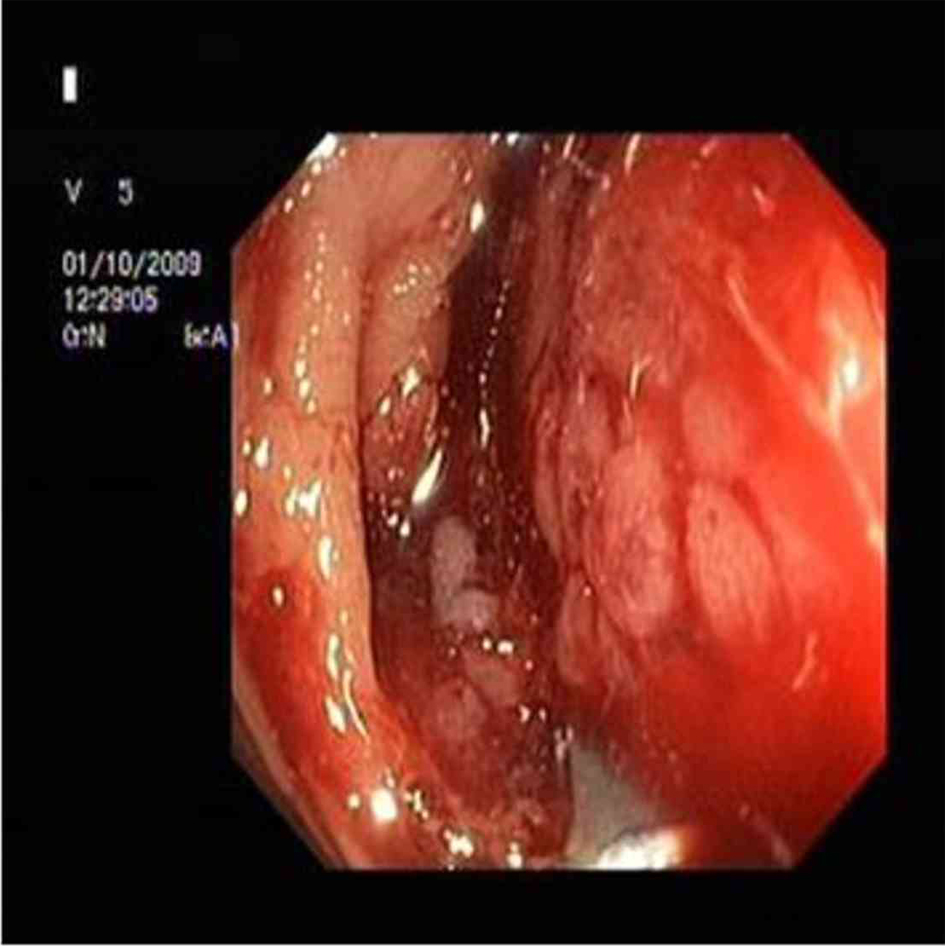

A 32-year-old male patient was referred to our gastroenterology clinics with complaints of melena, abdominal pain, constipation and weight loss. Physical examination was gave no abnormality. Initial laboratory studies revealed normal results, except for hemoglobin level as 9 g/dL and hematocrit 26%. Abdominal ultrasound and tomography revealed intestinal wall thickening (about 3.5 cm) presented throughout approximately 10 cm segment of bowel, at the right abdominal region. Colonoscopy showed a mass surrounding intestinal lumen and preventing transition of colonoscopic device to proximal near hepatic flexura of colon (Fig. 1). Despite colonoscopic biopsy was applied two times, tissue samples gave non-specific histopathological appearances because of probably taken a biopsy of necrotic areas. Open laparatomy operation was performed to the patient. In the operation, frozen section samples examination revealed that the tumor was malignant, therefore hemicolectomy, lymph node dissection and ileocolic anastomosis were performed. Postoperative macroscopic examination revealed a mass 8 x 7 x 7.5 cm in size, with tumoral formations which containing large necrosis areas that invading from intestinal mucosa to serosa. Postoperative staging was T3N1M0 (Stage III).

![]() Click for large image | Figure 1. A mass in proximal colon. |